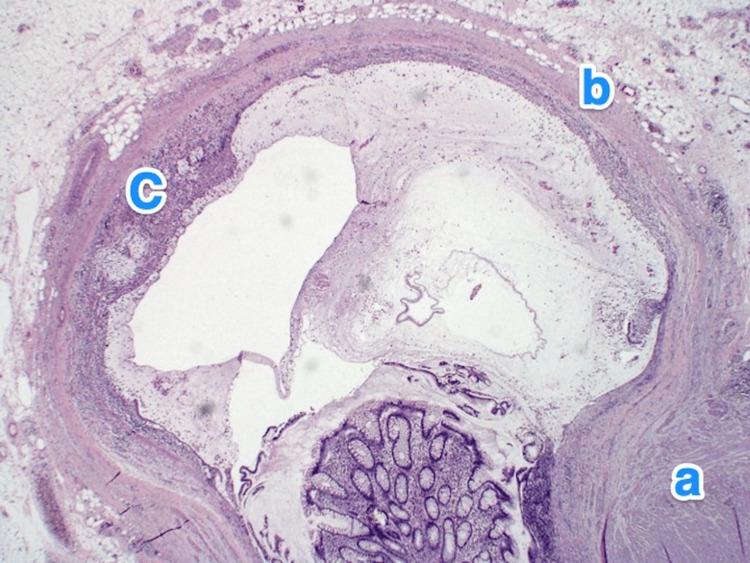

Appendicular diverticulitis (AD) is a rare entity characterized by the inflammation of the arising diverticulum of the appendix. It has been reported to carry a high risk of perioperative complications, such as bleeding and perforation. Furthermore, multiple articles have highlighted the importance of diagnosing AD early due to its strong association with malignancies. Limited published cases concerning AD in our country and globally are available in the literature. Hence, we present in this article a case series of five exciting cases of incidental findings of AD that were initially diagnosed as acute appendicitis based on clinical evaluation and imaging findings. In our series, we performed a retrograde evaluation of the computed tomography scans of all five cases that showed diverticula. In conclusion, histopathological evaluation remains the method of choice to reach the definitive diagnosis; however, it is essential to highlight the relevance of imaging in diagnosing AD preoperatively in the early stages to reduce morbidity and mortality.